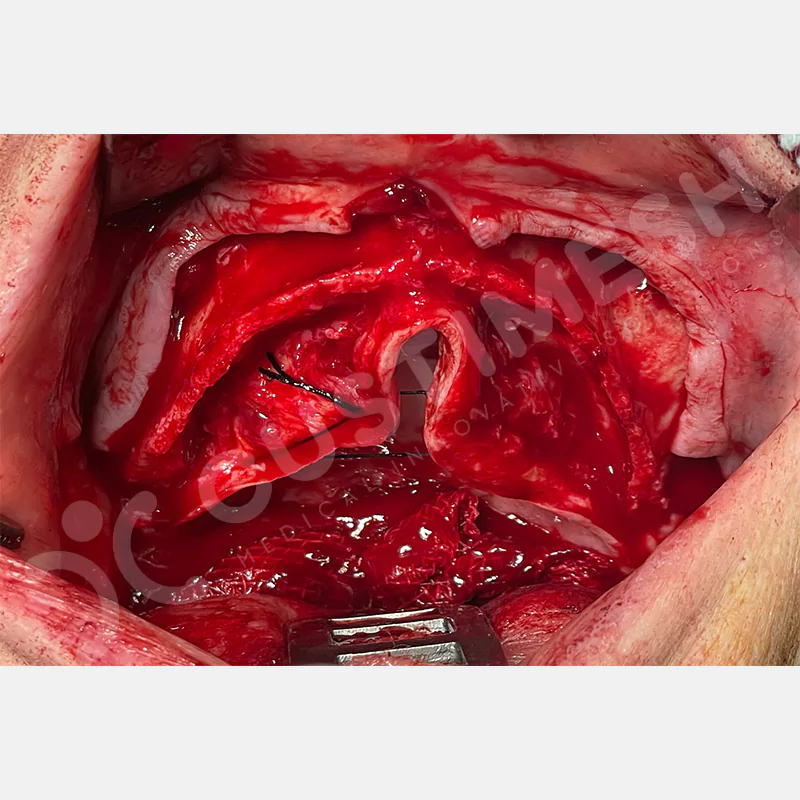

VAKA 1

VAKA 2

VAKA 3

VAKA 4